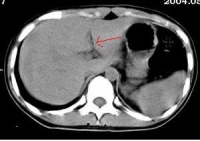

胃肠道穿孔的主要X线表现是气腹即腹膜腔内出现游离气体。关于气腹的显示方法,一般是采用透视与照片检查。尤其是少量气腹的显示则尤为重要,如病情允许,立

位透视并转动体位观察,此时往往能显示膈下新月形的游离气体的存在,因为气体总是具有浮游到腹腔最高处去的倾向,确定了膈下游离气体后,应即时照片以供临床参考。

在病情危重而不能坐或站立时,可采用仰卧侧位投照,此时气体可上升至前腹侧壁,可以见到腹壁与肝和肠之间有气层,使肝前下缘和肠外壁显示。

如情况只允许照仰卧位片时,只要能详细地认真阅片,亦可能发现有价值的征象:

一是见到明确的腹腔内脏器(胃肠和肝脾)的外壁;

二是腹腔内某些韧带(如肝脏前力的镰状韧带)的明确显示。见到这些征象

应考虑有气腹存在。如无气腹发现而临床又高度提示有急性胃肠道穿孔时,必要时可经胃管抽吸胃液后注入空气约300ml,则空气可从穿孔处逸出形成膈下游离气体,有助了胃、十二指肠溃疡穿孔的诊断。

胃肠道穿孔的传统诊断方法为摄取腹部X线平片,观察膈下、腹壁下有无游离气

体,以此作为主要诊断依据,但是准确性有限。